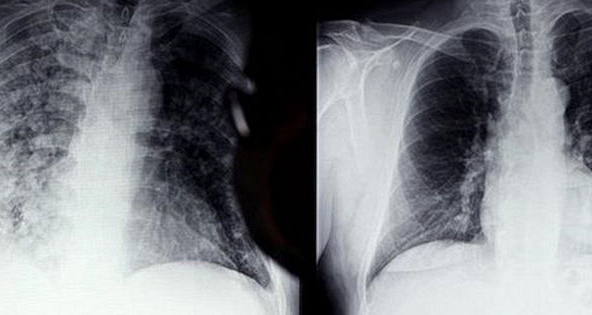

Các triệu chứng thường gặp ở những người từng mắc COVID-19